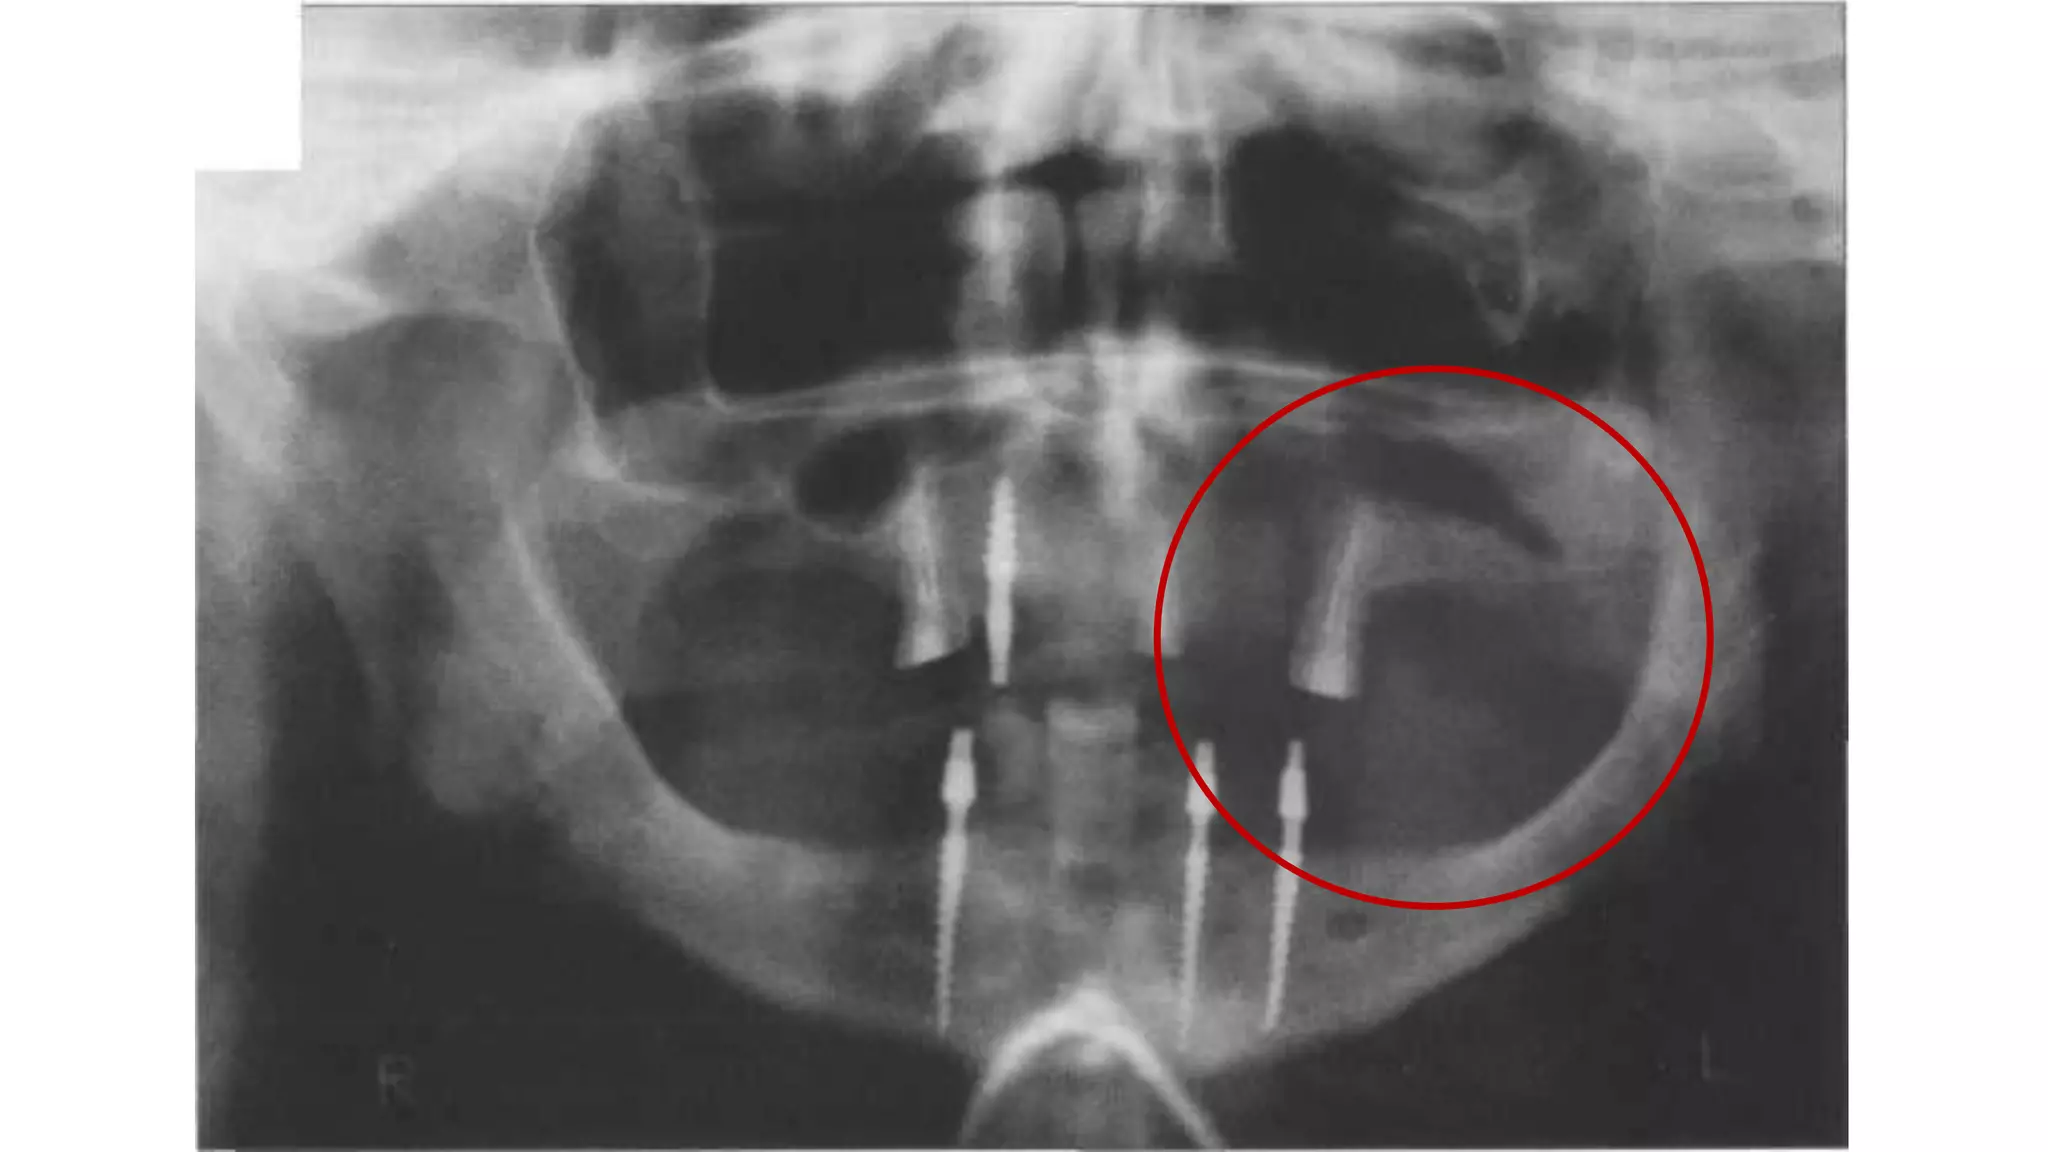

АМЕЛОБЛАСТОМА

Амелобластома – это доброкачественная одонтогенная опухоль челюстно-лицевой

локализации, вызывающая деструкцию костной ткани. По мере развития

амелобластомы возникает асимметрия лица, происходит постепенная деформация

челюсти, расшатывание и смещение зубного ряда

АМЕЛОБЛАСТОМА Амелобластома – этодоброкачественная одонтогенная опухоль челюстно-лицевой локализации, вызывающая деструкцию костной ткани. По мере развития амелобластомы возникает асимметрия лица, происходит постепенная деформация челюсти, расшатывание и смещение зубного ряда